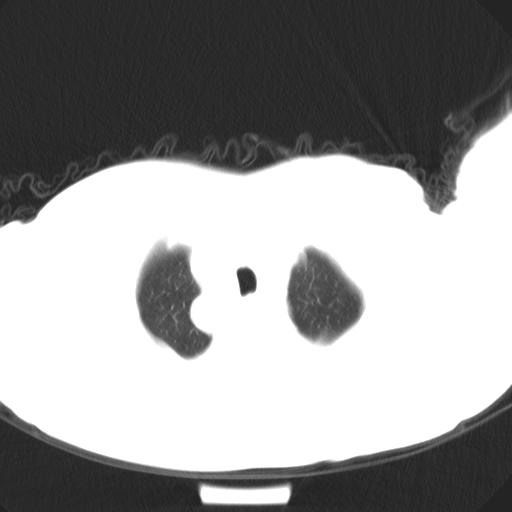

标题: CT25454:男,51岁,体检时发现右上纵隔高密度影。请会诊! [打印本页]

标题: CT25454:男,51岁,体检时发现右上纵隔高密度影。请会诊!

男,51岁,体检时发现右上纵隔高密度影。

考虑后纵隔神经源性肿瘤。

考虑右后上纵隔神经源性肿瘤。

右上纵隔脊柱旁圆形结节,密度均匀,边界清楚——考虑神经源性肿瘤!

考虑后纵隔神经源性肿瘤(神经纤维瘤)

考虑后纵隔神经源性肿瘤,或支气管囊肿不除外。

神经源性肿瘤,次之castleman';s diease